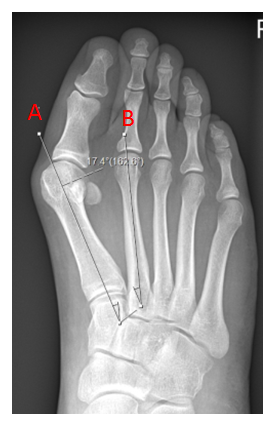

This X-ray shows a significant bunion (hallux valgus) only. The first metatarsal (a) in isolation has drifted away from the second (b)

This X-ray shows a bunion, however the metatarsus adductus angle is significant, reflecting the medial drift of the first three metatarsals towards the inside of the foot. Now the bunion cannot be corrected by just addressing the first metatarsal alone.

The far X-ray shows the bunion and metatarsus adductus angles having been successfully addressed by fusion the medial three metatarsals with screw fixation.